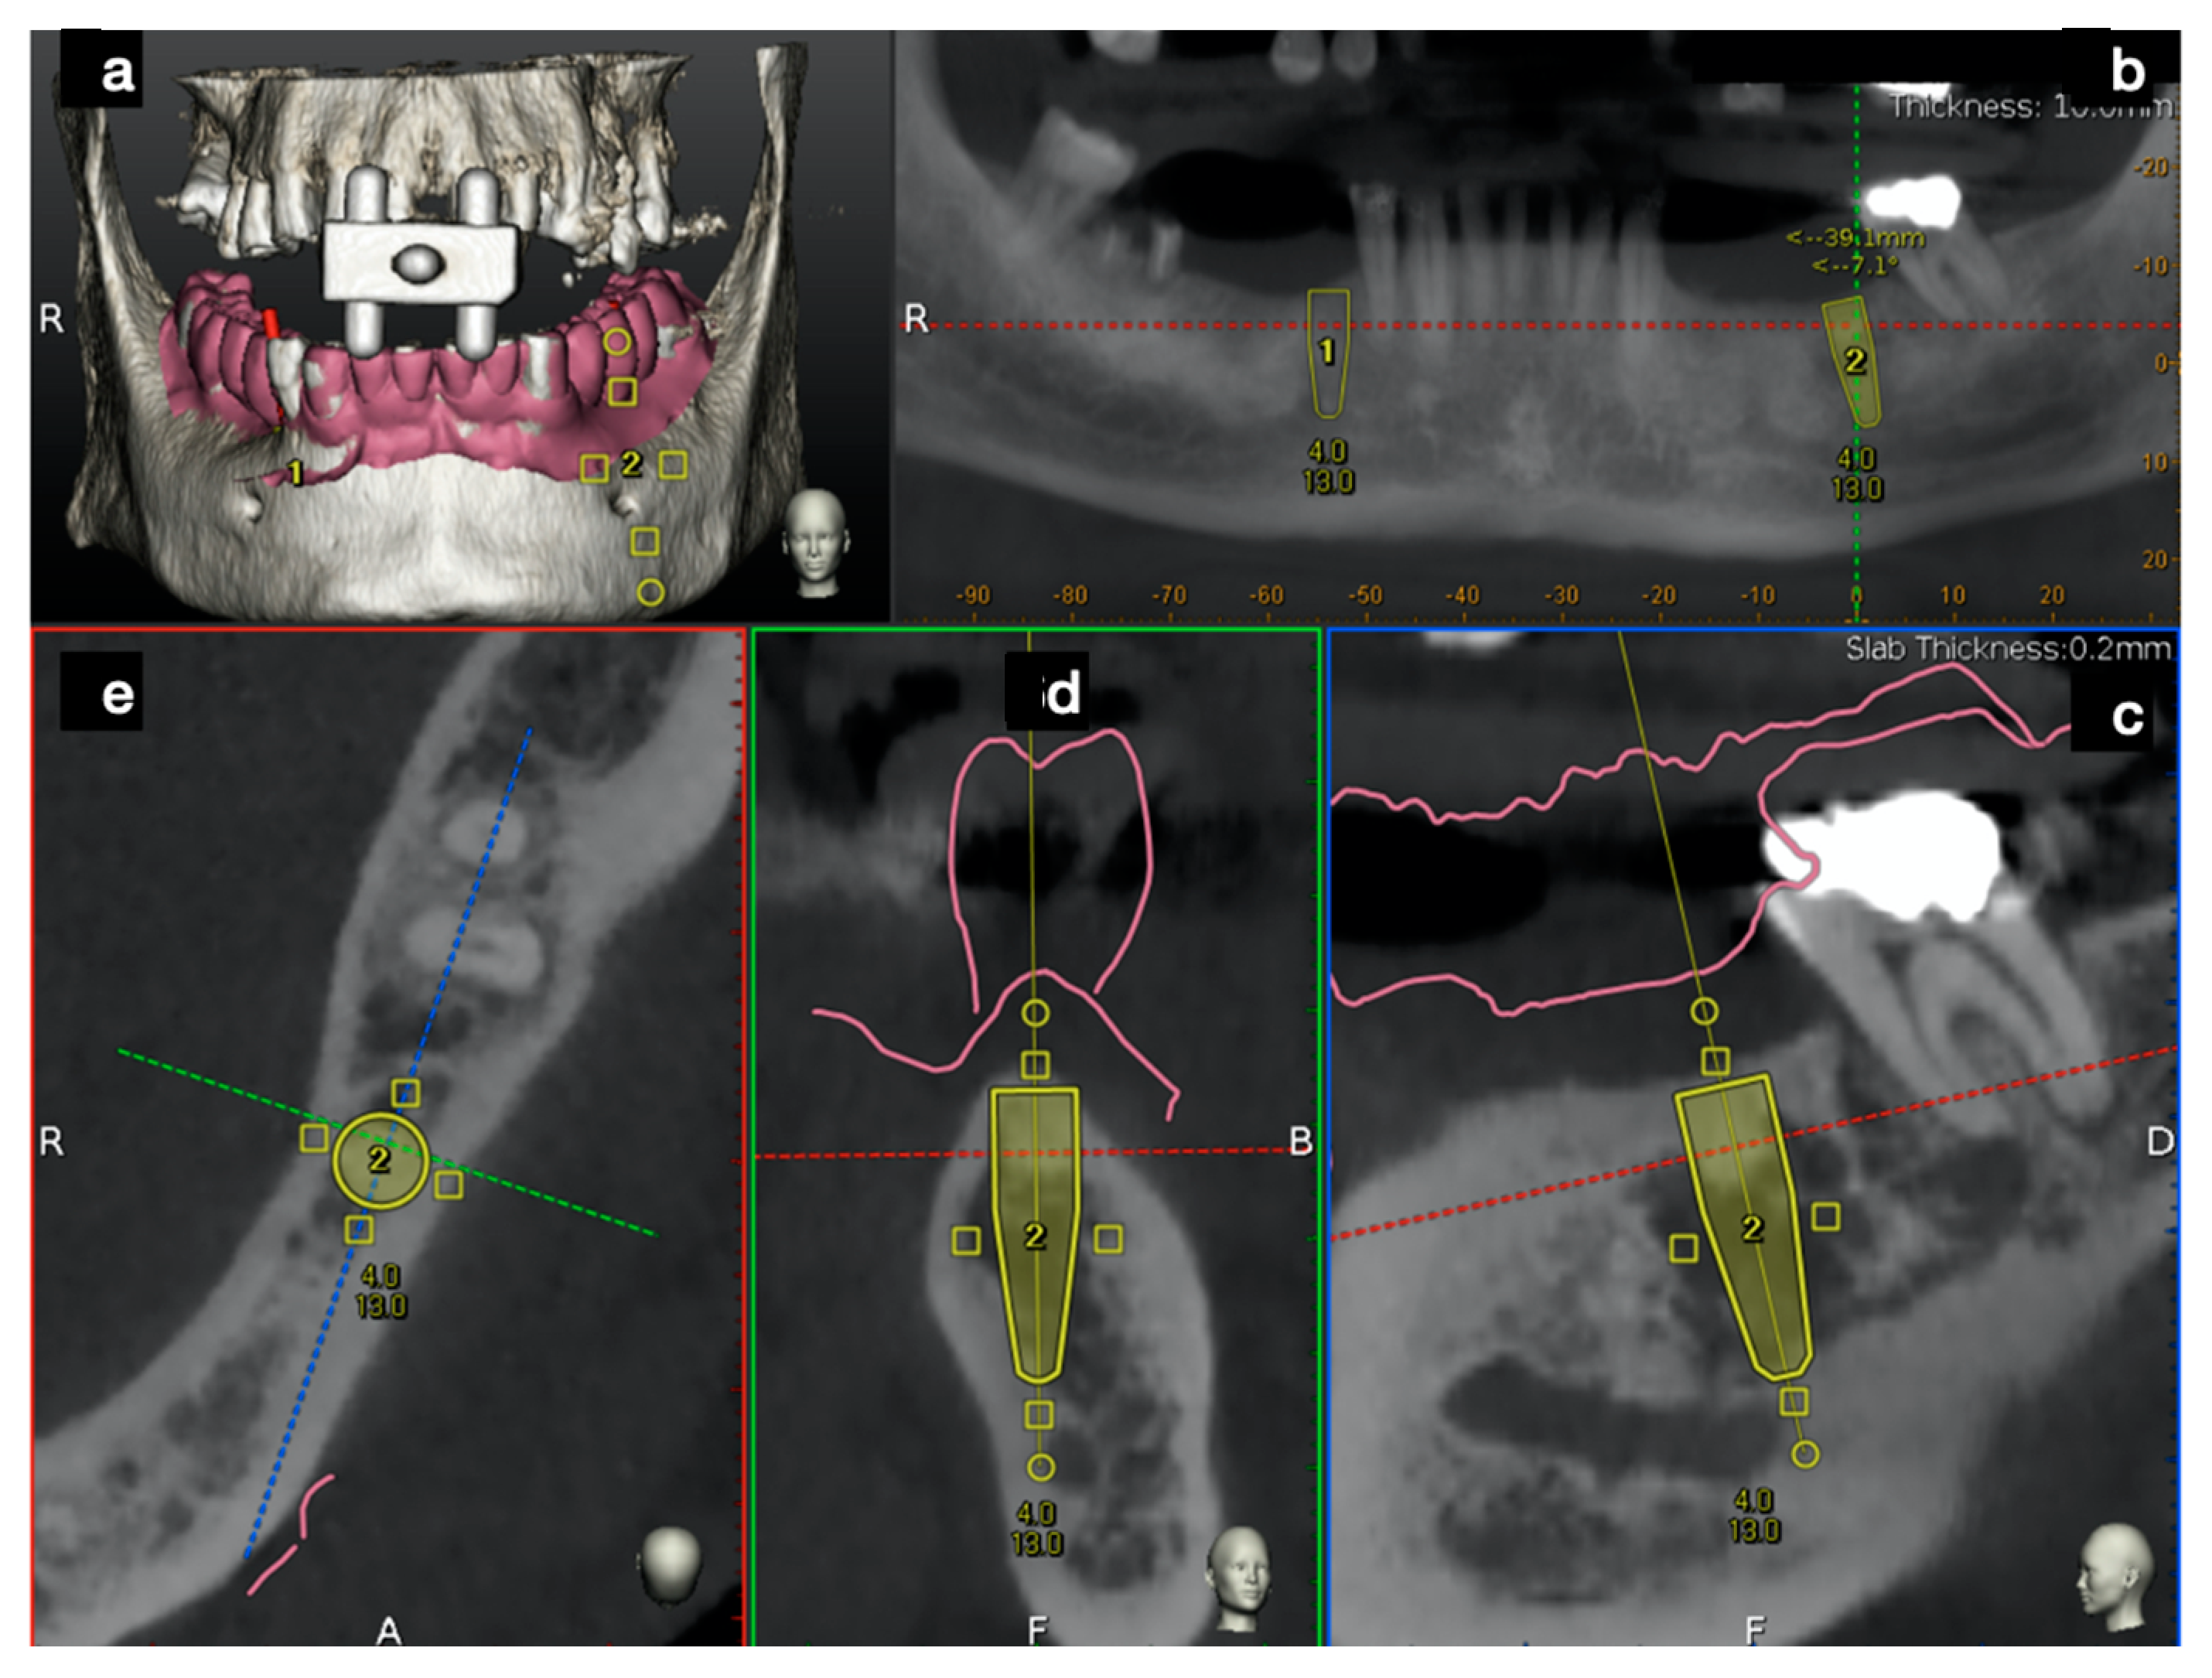

2.2.1. Plan

2.2.2. Trace

2.2.3. Place